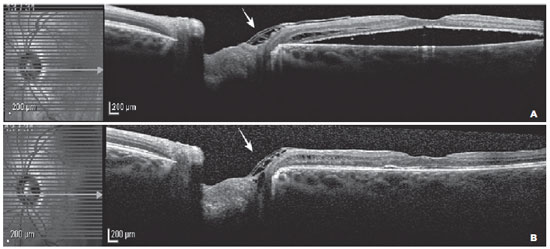

A 27-year-old woman presented with visual loss over the last 4 months. On ophthalmologic examination, her best-corrected visual acuity (BCVA) was 20/20 in the right eye (OD) and 20/60 OS. The anterior segment examination was normal in both eyes. Fundus examination OD was unremarkable, whereas OS fundus examination and optical coherence tomography (Spectralis OCT Heidelberg Engineering, Heidelberg, Germany) showed an ODP with SMD (Figure 1).

11-fig01tb.jpg)